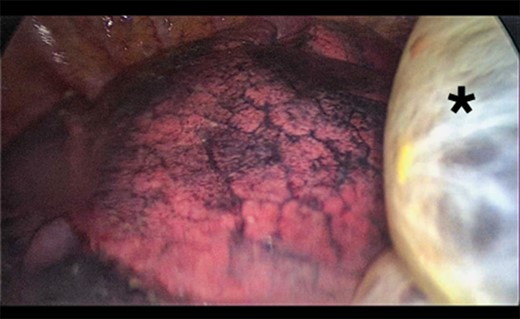

A 73-year-old male patient with a clinical history of COPD, lung emphysema and a 30-year smoking history was admitted to the ED due to a 24-h clinical picture of dyspnea immediately following a sudden bout of dry coughing. Physical examination showed a dyspneic patient, tachypnea of 25 rpm, heart rate of 85 bpm and blood Pressure of 135/75 mmHg along with central cyanosis. Chest exam showed a hyper-resonant right hemithorax along with reduced breath sounds. Initial chest X-ray revealed a large right-sided pneumothorax (Fig. 1). A right chest tube was placed in the ED. Emergency echocardiogram had no significant findings and spirometry showed suspected patterns of obstruction. Following patient stabilization, a high-resolution chest computed tomography (HRCT) was performed revealing extensive pan lobar emphysema throughout both lungs, para septal emphysema in both the anterior upper lobes and herniation of a left lung bullae through the anterior mediastinal pleura along with a right-sided pneumothorax with the chest tube in place with persistent air space (Fig. 2). The patient was taken to surgery where a right video-assisted thoracoscopic (VATS) approach showed severe lung emphysema and a contralateral herniated left lung bulla through the mediastinal pleura anterior to the pericardium (Fig. 3). Right pleurodesis was performed using Talc and a left posterior thoracoscopy showed a severe emphysematous left lung with a lingular herniated bulla to the right hemithorax through an anterior mediastinal pleural defect along with pleural adhesions (Figs 4 and 5). Thoracoscopic hernia reduction was performed along with bullectomy using 60 mm mechanical sutures (Fig. 6). Chest tubes were removed on POD 3 (right) and POD 4 (left). The patient had significant respiratory improvement and was discharged on POD 5.

Thoracoscopic view from left side of transmediasinal hernia of pulmonary bulla after reduction (asterisk).